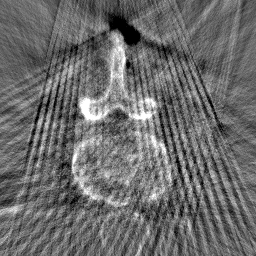

Disentanglement and explicit shape constraints. As shown in Fig. 4, we can see streak metal artifacts nearly everywhere in . M1 can roughly disentangle artifacts and anatomical information but strong vertical artifacts and strange air area appear in (see red arrows of M1 in Fig. 4). For the anatomical structure, M1 learns to segment vertebrae with fully supervised and applied on various CT images, but fails to suppress the false bony structure in and as may misclassify some metal artifacts as bone.

Implicit shape constraints. With , all segmentations are improved with higher Dices and smaller ASDs, see Table 1. As shown in Fig. 4, , and become similar but the high density bone is not correctly segmented in as it maybe treated as metal artifacts. Comparing between M2 and M1, the abnormal air region disappears but metal artifact reduction performance is still not satisfactory.

Anatomy-aware generation. With AADE layer in M3, , and are substantially improved as shown in Table 1. Note, is used as attention map, so we do not expect it to be identical to . In , metal artifacts are further suppressed comparing with M2. Thus, AADE is critical to our anatomy-aware artifact disentanglement framework. With the special structure, can be punished in the image translation and reconstruction processes and the other encoders and generators receive more guidance. However, as shown by blue arrows in Fig. 4, we observe a shadow of vertebra edge of appears in of M3 and the vertebra boundaries get smoothed out in . It may be because sharp edges are encoded as metal artifacts and forced to be added to by artifact consistency loss .

Removal of . To mitigate vertebrae shadows, we remove . The segmentation performance of most images in M4 gets improved because of better synthetic images. Overall, in M4 yields the best segmentation performance for CBCT images with an average Dice of 0.847 and an average ASD of 1.54 mm. For the synthetic images, M4 generates with the best quality and least metal artifacts among all the models. M4 also outputs without vertebra shadows. The results indicate our shape-aware network could preserve anatomical details and transfer the metal artifacts precisely without .